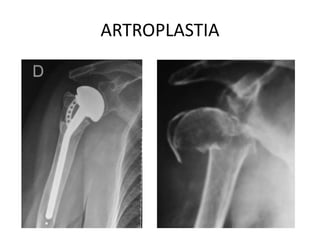

ARTROPLASTIA

TRATAMIENTO • FIJACION EXTERNA •REDUCCION CERRADA CON FIJACION PERCUTANEA • RAFI • REEMPLAZO TOTAL O PARCIAL DEL HOMBRO